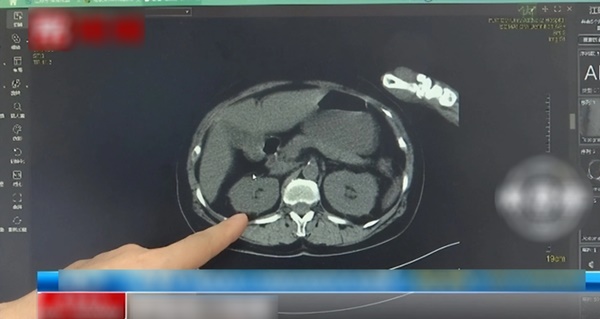

Sau khi điều trị bằng thuốc chống nhiễm trùng có mục tiêu, cô Du đã may mắn qua cơn nguy hiểm và có thể sửa chữa lại lỗi sai của bản thân. Trong quá trình điều trị, bác sĩ phát hiện nguồn lây nhiễm toàn thân của cô Du rất có thể đến từ hệ thống tiết niệu.

Theo các bác sĩ, nhiễm trùng đường tiết niệu là thuật ngữ chung chỉ các bệnh nhiễm trùng ở nhiều bộ phận khác nhau của hệ tiết niệu như thận, niệu quản, bàng quang, niệu đạo. Căn bệnh này có tỷ lệ mắc cao và là bệnh truyền nhiễm phổ biến thứ hai trong cơ thể con người sau nhiễm trùng đường hô hấp. Nó ảnh hưởng lớn đến chất lượng cuộc sống của người bệnh. Phụ nữ có 60% khả năng mắc bệnh trong suốt cuộc đời.